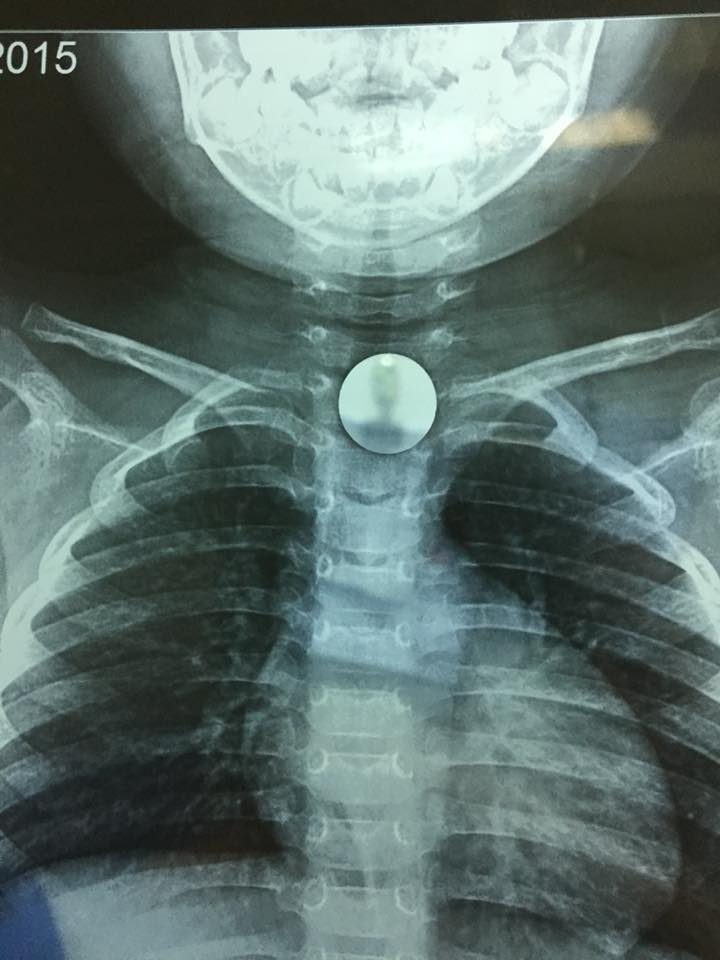

Hình ảnh đồng xu chắn ngang cuống họng bé K qua chụp Xquang.

Ngay khi tiếp nhận trường hợp của bé K, các bác sĩ bệnh viện đa khoa Đức Giang đã nhanh chóng chỉ định chụp phim Xquang vùng ngực - cổ để xác định vị trí dị vật. Hình ảnh Xquang cho thấy dị vật là một hình tròn giống đồng xu vị trí ngang giữa cổ. Dị vật mắc kẹt có cạnh tròn xung quanh nên không gây tổn thương niêm mạc.